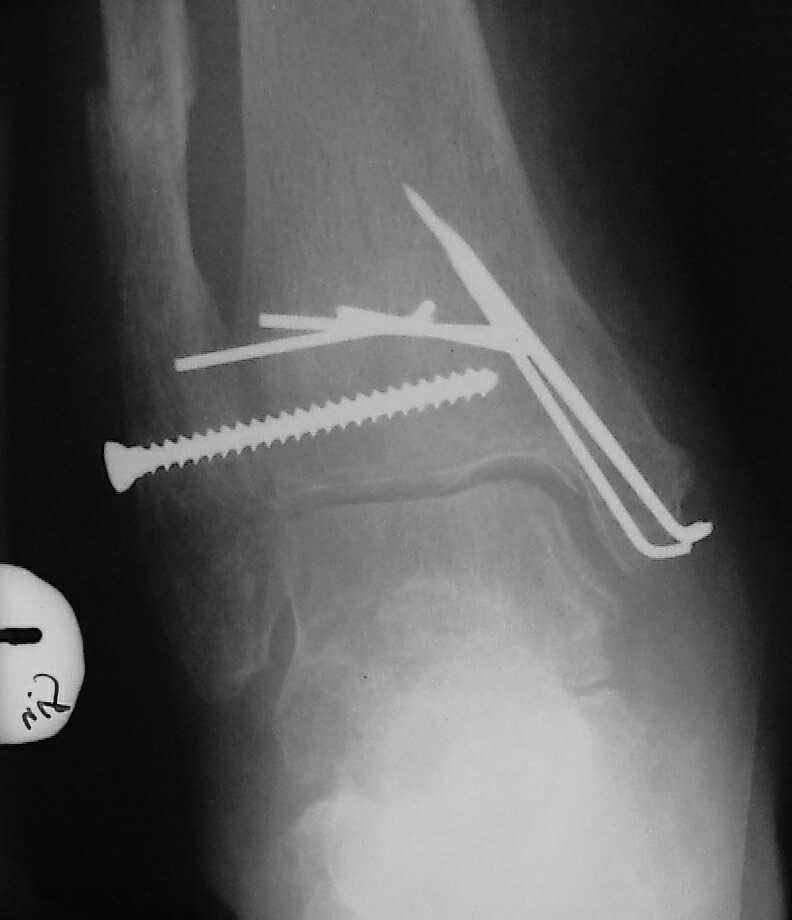

При поступлении - закрытая репозиция, повторная в связи с большим отеком через неделю, подготовлена к остеосинтезу в первых числах декабря. Заживление без осложнений. Циркулярный гипс - 7 недель, снят,часть спиц удалено 20 февраля т.к.пальпировались под кожей, постепенная нагрузка, проблем нет до середины апреля когда появильсь боли с мед. стороны сустава и локалная гиперемия ( трактовалась как флеботромбоз). Повторное поступление 15 апреля - усиление болей,пов. температура, локально выраженная гиперемия.Локально выделений нет. На RTG - деструкция в области мед лодыжки и заднего края. Сахар крови умеренно повышен. Как трактовать проблему, какой диагноз и тактика лечения? Заранее спасибо, Владимир.

Диагноз я бы поставил: неправильно срастающийся перелом обеих лодыжек и заднего края ББК. Ложный сустав мед. лодыжки? Хронический вялотекущий остеоимиелит голеностопа. Сопутствующий - СД, диабетическая ангиопатия 2.

Ретроспективно, на Ваш взгляд, что изменилось бы при остеосинтезе более массивными имплантами?(выбор в пользу спиц как раз и был из-за минимального объема оставляемых имплантов) Иммобилизация 7 недель это очень длительно? Результат на 4 RTG - в чем нефункциональность? - согласен, что репозиция заднего края не была достигнута. Какие признаки ложного сустава мед. лодыжки ?

Уважаемый Владимир. Нестабильность и нефункциональность, как мне видится по снимочкам, была изначально,об этом ниже В чём вы видите массивность третьтрубчатой, например титановой 1.5 мм пластины? Ими оперируют во всём мире и получают хорошие результаты, а почему у нас это массивно мне непонятно.Спицевая "тюрьма" хороший способ, но только для временной интраоперационной фиксации, хотя лично я редко пользуюсь, на то есть костодержатели для малых фрагментов и репонирующие винты. Кстати в данном случае, при её остеопорозе лучше было бы поставить LCP (опуская финансовую сторону вопроса, в теории). А вот функциональность - при правильном подборе и установке металлоконструкций пациент нуждается в иммобилизации на срок заживления швов, а уж потом ходьба без нагрузки на оперированную конечность 6 недель - (базовый курс АО). Ретроспективно, как мне видится, при хорошей репозиции и фиксации всё бы консолидировалось, хотя на всё воля божья, но по крайней мере не нужно было бы удалять железки. Иногда ставишь всё как мама родила, а потом очень плохие последствия. Признаки ложного (?) я вижу на снимках,хотя это может быть и банальное отсутствие консолидации за столь длительный срок, что само по себе я бы расценил как ложный сустав. А что Вы сами думаете по этому поводу? И как планируете артродезировать? (если планируете). Мне кажется, самое обидное то, что и эндопротез голеностопного поставить там просто некуда. Я бы думал об очень сомнительном прогнозе.

По стихании обострения - артродез голеностопного сустава был бы окончательной операций, обеспечивающей опорную и безболезненную конечность. Мы бы сделали L-образным доступом параллельно переднему контуру наружной лодыжки с уходом кзади, с пересечением малоберцовой кости вверху раны и отворотом единого кожно-костного лоскута, с последующей продольной остеотомией малоберцовой кости для обнажения губчатой кости; такой доступ дает очень хороший обзор суставных поверхностей таранной и большеберцовой костей для сятия хрящевого покрова. Фиксация аппаратом из двух опор - по паре спиц в таранной и

большеберцовой костях, наружную лодыжку прижать спицей с упором (лучше в виде петли) к продольному пазу, сформированному по латеральной поверхности сочленяющихся костей.